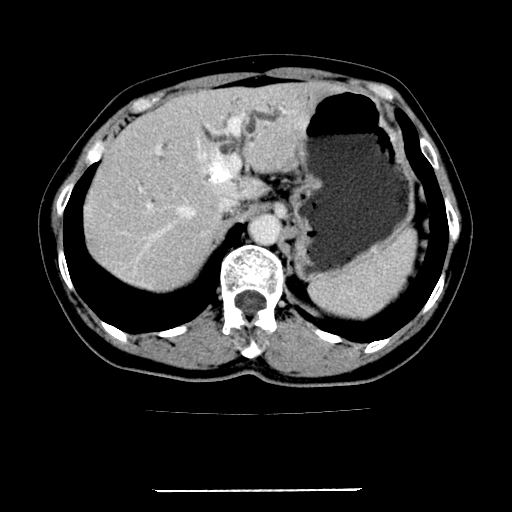

女,67岁,上腹部疼痛一周伴皮肤黄染,无发热。

左叶肝内胆管结石,并远端肝内胆管扩张。

考虑:肝内胆管结石继发肝内胆管扩张,右肾旋转不良。

肝内外胆管结石并肝内胆管扩张。

肝内外胆管扩张,左叶胆管内结石

建议薄层观察,除外肝门部胆管细胞癌

1、肝门高密度影下层面和胰头层面可见轻度胆管扩张,而静脉和延迟期均未见扫描完胰头,不能完全排除胰头占位。2、肝门部高密度影,考虑钙化或结石。

考虑肝门胆管癌伴门脉左支受侵包埋,建议mrcp进一步检查。